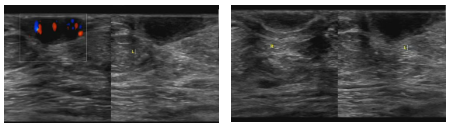

超声检查提示“考虑乳腺Paget病(乳腺湿疹样癌)可能”,术后病理结果确诊为(左侧)乳腺Paget病(乳腺湿疹样癌)。

特别提醒:若出现乳头或乳晕反复瘙痒、脱皮、溢液等症状,务必及时就医检查。超声检查对致密型乳腺组织穿透力较强,可通过彩色多普勒显示血流信息,借助弹性成像判断肿块硬度,诊断可信度较高;超声引导下穿刺活检及超声增强造影,能进一步提升诊断准确性。